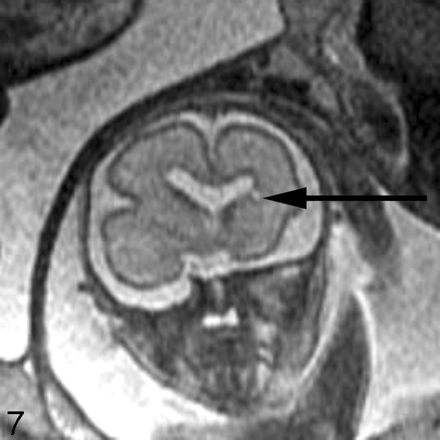

Destructive lesions generally appear as small periventricular areas of T2 hyperintensity, focal defects or irregularities in the germinal matrix, or larger areas of abnormal signal intensity (with or without volume loss) involving the developing white matter and overlying cortex (Fig 7). Subtle irregularities of the ventricular margin may also be an indication of injury to the adjacent germinal matrix and/or overlying developing white matter. Hemorrhage usually appears as a hypointense area on T2-weighted images and hyperintense area on T1-weighted images, though the signal intensity can vary depending on the stage of hemorrhage. Intraventricular hemorrhage can appear as debris layering in the dependent portion of the ventricle or as a focal hematoma (Fig 6B). The detection of small subependymal hemorrhages is more difficult, partly because the normal germinal matrix has similar signal intensity to blood (hypointense on T2-weighted images and hyperintense on T1-weighted images) because of its high cellularity (Fig 8). T2* weighted gradient-echo sequences may be useful to help to confirm the presence of blood, because the hemorrhage appears more hypointense than the germinal matrix.

Coronal ssFSE T2-weighted image in a 25-week old fetus demonstrates a focal area of T2 hyperintensity adjacent to the frontal horn of the left lateral ventricle (arrow). This was also confirmed on axial image (not shown) and is consistent with an area of parenchymal injury. The lateral ventricles are mildly dilated (measuring 12–13 mm on sonography).

Coronal ssFSE T2-weighted image in a fetus at gestational week 23 demonstrates prominent hypointensity in the right caudothalamic groove (arrow) consistent with a germinal matrix hemorrhage.